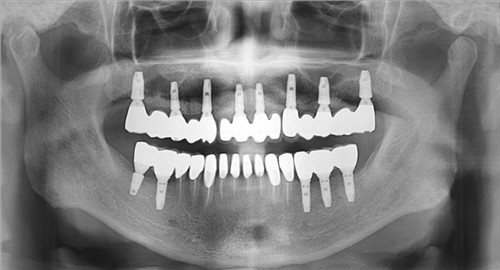

龍崗醫院的種植牙多少錢,這個(ge) 需要看龍崗醫院是否有世界各地的種植體(ti) ,因為(wei) 大家都知道種植牙是由人工牙根、基台以及牙冠三個(ge) 部分組成的,而種植體(ti) 的價(jia) 格是主要的一個(ge) 部分,一般情況下的,歐美的種植體(ti) 價(jia) 格要上萬(wan) 元左右,東(dong) 南亞(ya) 的種植體(ti) 價(jia) 格在數千上萬(wan) 元左右。